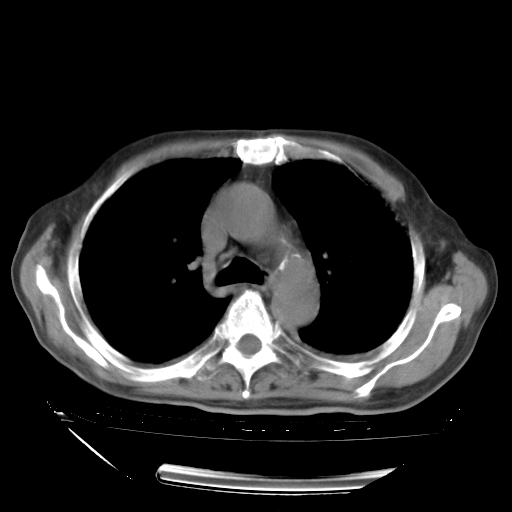

经过24天治疗,岳父的病情基本稳定。生活基本可以自理,可以下床活动。呼吸困难早已消失。体温基本正常。

只是甲强龙用80mg时血小板升到正常,改为60mg后又降到63×10*9/L。

主要治疗甲强龙80mg×14天,60mg×10天;同时抗结核(异烟肼+利福平+乙胺丁醇)。环磷酰胺0.1 tid 10天。

特别感谢胡教授、高管、桃子版主给出关键的治疗建议。桃版把所有肺部影像和全部临床资料请所在医院呼吸科、感染病科、结核科、临床免疫科专家会诊。临床免疫科专家制定了完整的治疗方案。